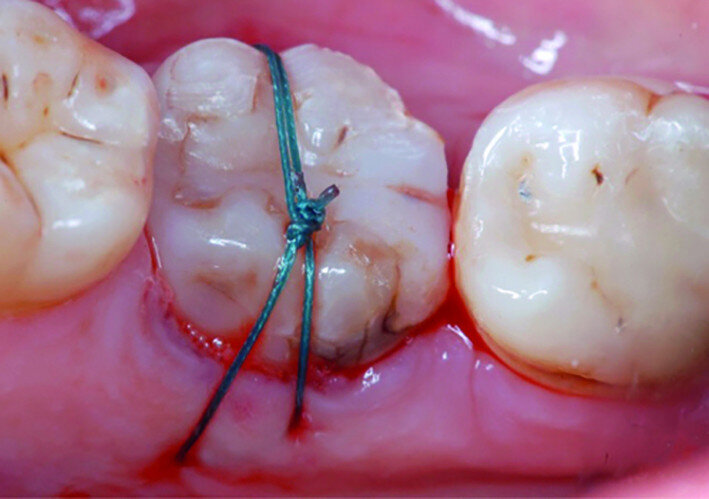

Fig. 8: Transplanted tooth sutured, immediately after surgery.

Dental autotransplantation is effectively a planned avulsion and replantation in the least traumatic way. Local anaesthesia is administered and prophylactic antibiotic administration is also recommended. Preparation of the recipient site includes extraction of any root remnants and debridement, and then the donor tooth is atraumatically extracted. A loose fit of the transplanted tooth in its new socket is generally recommended. In some cases, when the donor tooth fit is satisfactory, no further preparation of the new socket is required and the donor tooth is directly placed into the fresh extraction socket. If this is not the case, an atraumatic preparation of the new socket using surgical burs or implant drills is performed. The transplanted tooth is then tried in the recipient socket and relative adjustments are made if needed. In the meantime, the tooth is kept in the donor socket or in saline solution. The transplanted tooth should be placed slightly below the occlusal plane. Once proper fit and position have been achieved, the transplanted tooth is fixed with horizontal mattress sutures crossing over the occlusal plane. Postoperative care consists of oral hygiene and dietary instructions; a recall appointment is usually scheduled for after seven to 14 days for the removal of the sutures.

After local anaesthesia with 2 per cent mepivacaine with 1:100,000 adrenaline, the right maxillary second molar was atraumatically extracted. Initially with a size 15c surgical blade, the periotomy was realised and then the tooth was extracted after separating the roots to avoid unnecessary trauma to the alveolar bone. Then the donor right maxillary third molar was extracted after periotomy as described and transplanted into the adjacent site. Because of the slight differences in the root anatomy, it was necessary to remove the intraradicular bone septum of the receiving site to al- low tooth positioning, and a odontoplastic of the donor tooth crown was performed to maintain it not in occlusion. An antibiotic (amoxicillin/clavulanic acid, 1 g, by mouth twice a day for five days) was prescribed, along with rinses with 0.2 per cent chlorhexidine. The tooth was keep stable with sutures (Fig. 8). A periapical radiograph was taken (Fig. 9). At the suture removal at two weeks, the tooth showed good stability, and positive adaptation of the soft tissue was observed (Fig. 10). At four weeks, the tooth was stable and the soft tissue looked healthy (Fig. 11). The patient did not show any adverse effects and stated that the tooth was fully functional. Examination of the avulsed second molar showed the extent of the perforation (Figs. 12 & 13).